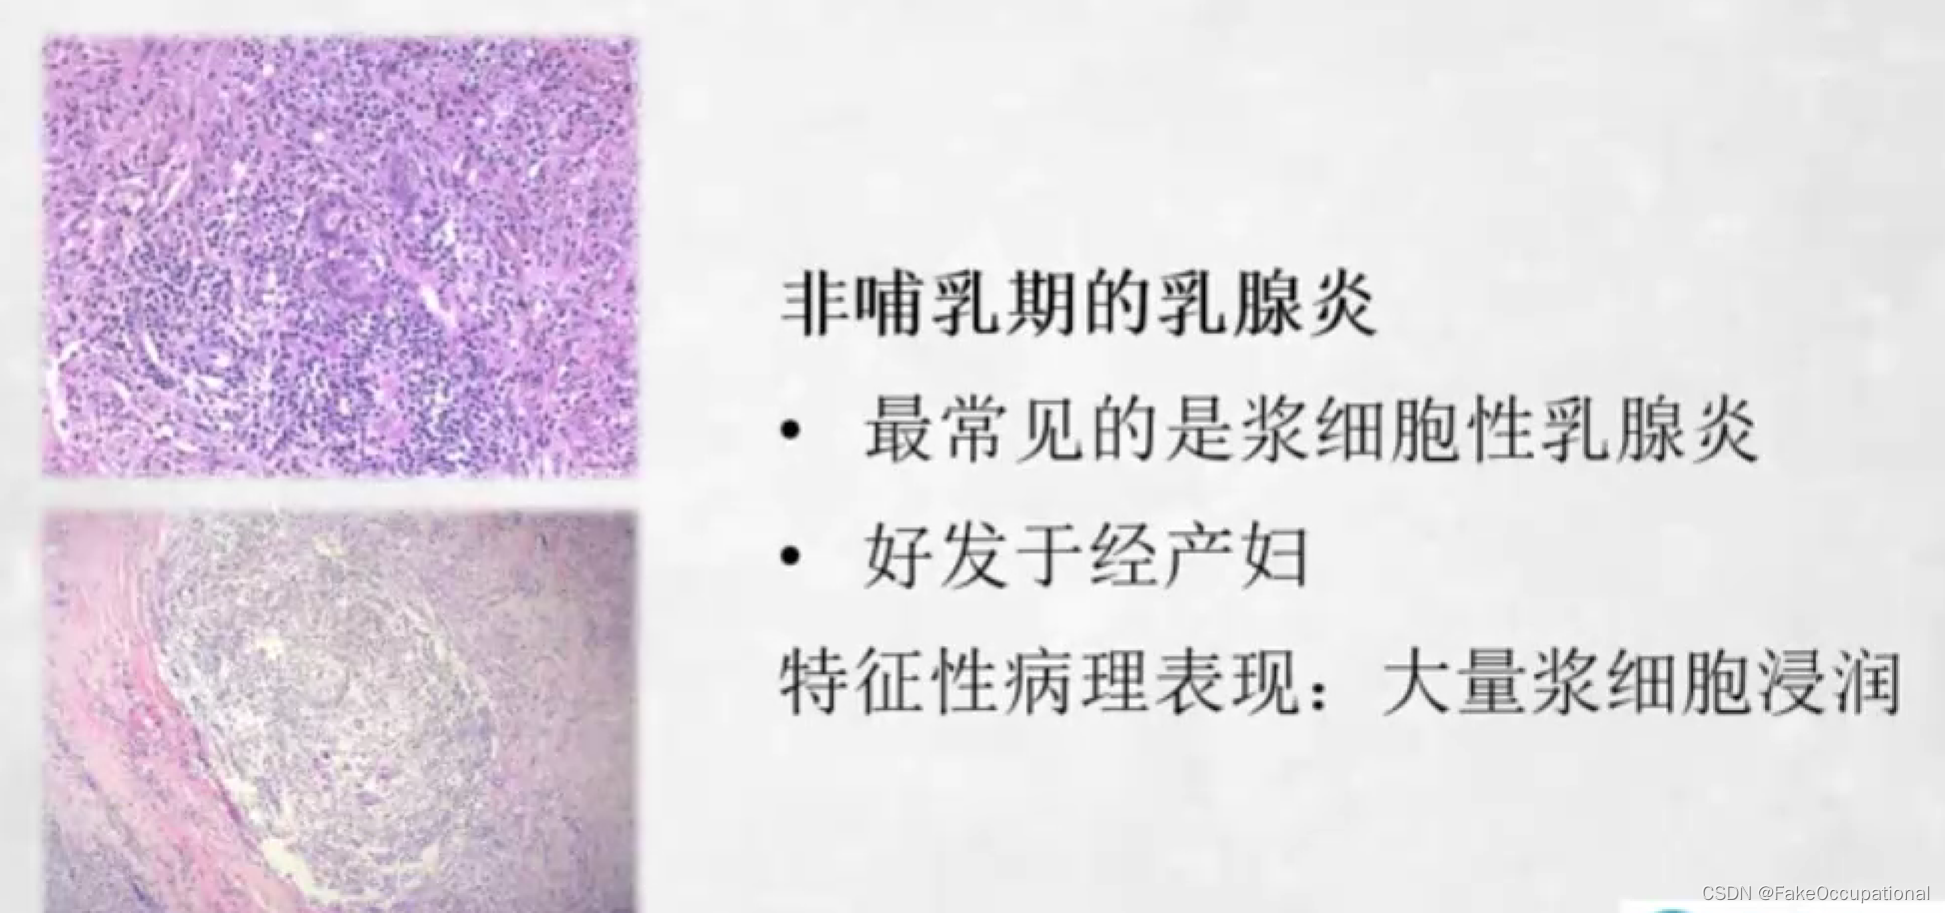

乳腺炎

- 临床表现有不同程度发热患处乳腺红肿、疼痛、乳腺肿块患侧腋下淋巴结肿大